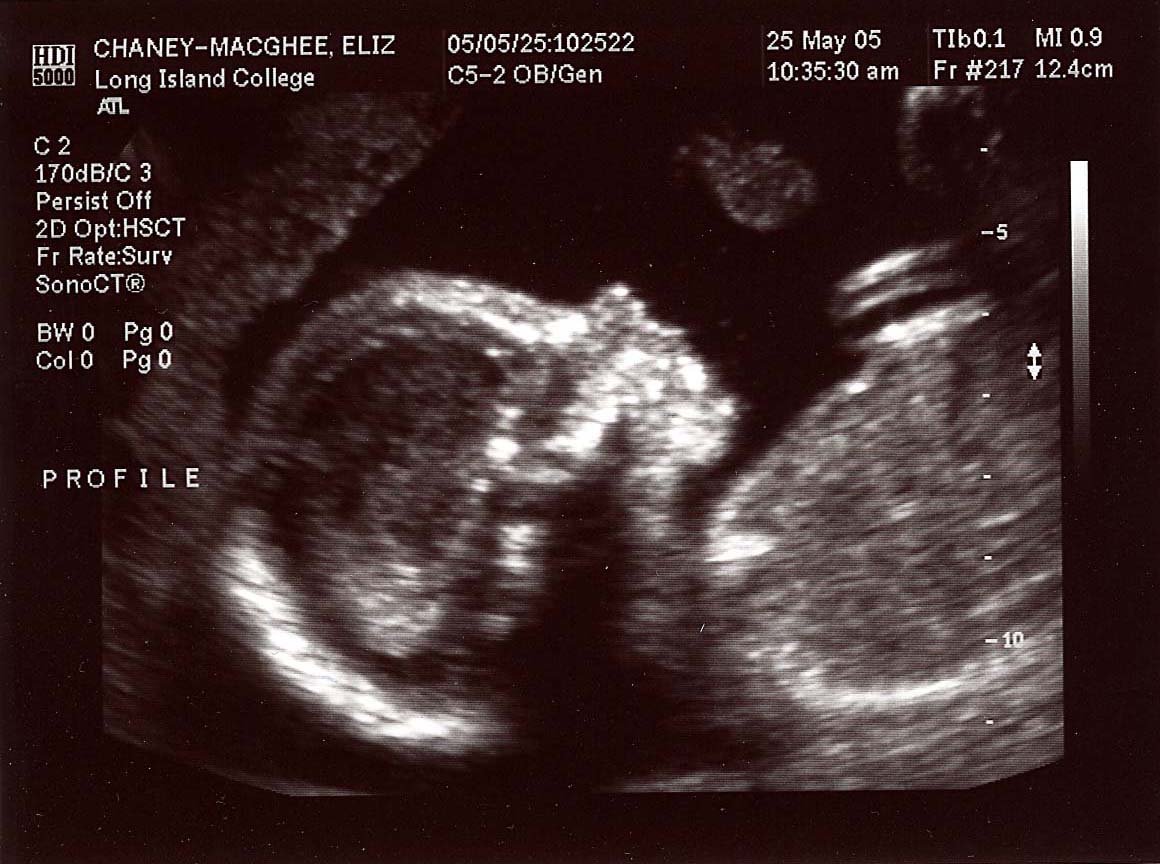

20 week series:

images taken 5/25/04, baby's weight estimated at 12 oz.

Close up, profile; 20 weeks.